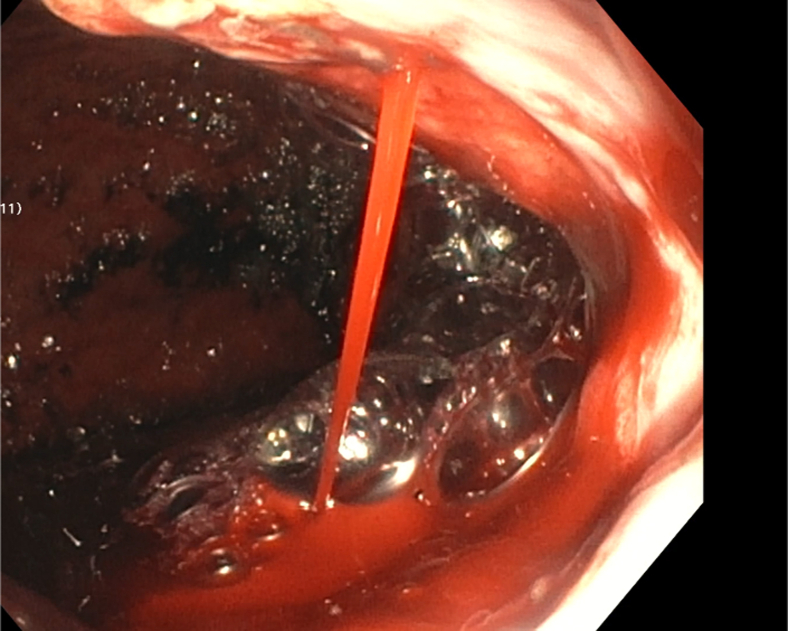

Figure 4.

An active spurting varix at the gastroesophageal junction seen on EGD.

In case 1, a 38-year-old male patient with a history of recurrent upper GI bleeding presented to the emergency department for hematemesis and coffee-ground emesis. The patient was hemodynamically stable. The external receiver indicated that blood was detected by the SOS capsule, and total monitoring time was 5 minutes and 13 seconds (Fig. 3). The patient underwent an EGD after 1.5 hours of capsule administration, which showed large varices in the lower third of the esophagus and an active spurting varix at the gastroesophageal junction that was actively pouring red blood into the stomach (Fig. 4). A total of 6 bands were successfully placed. A follow-up abdominal radiograph performed 3 days after capsule administration confirmed the SOS capsule had been excreted from the body (Fig. 5).